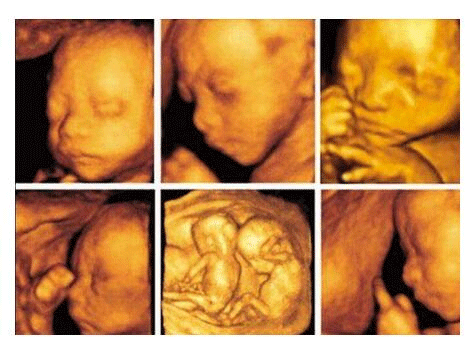

三维彩超,即彩色多普勒超声检查的一种,检查图像呈土黄色,通过多普勒超声仪器发出超声波,对体内各项器官进行成像。三维即其图像是立体的,可以更直观的看到器官的形态,及时发现病变并进行治疗。三维彩超常用于产检,用来判断胎儿的生长发育的情况或是否出现畸形等。

产检中,三维彩超通过测量子宫纵径、子宫体横径、子宫前后径这三条径线来观察胎儿是否正常。以及通过三维立体的成像,可以清晰的显示出胎儿各个内脏器官,以及面部器官、四肢的情况,来简单的判断胎儿是否存在畸形,包括胎儿是否患有先天性心脏病也是能够检查出来的。

24周的胎儿,其身体结构的生长发育已经很完善了,且胎儿大小也很合适,这时候做三维彩超可以很直观的看到胎儿的五官四肢、以及内脏器官,还能了解胎儿双顶径、头围、腹围、股骨长等发育情况。

2、清晰度不同

目前临床上三维彩超检查是直接对胎宝宝先天头面部畸形的判断,可以拍到宝宝生长发育的局部立体图像。而四维相对于三维来说,会更清晰,对胎宝宝畸形,如唇腭裂、四肢发育畸形、脑膜膨出、脊柱裂、腹壁裂和心血管畸形等能够做早期诊断,并且能够立体显示胎宝宝的颜色、各器官的发育情况,甚至在母体内吸吮、睡觉等动态也可以捕捉到。。

三维和四维并不是彩色图片,只是和黑白色有差异,二者呈现的都是土黄色的画面。但三维的成像是静态的,是一张图片,而四维彩超则是动态的,像一张动图一样,并且有的医院会允许刻成光盘带回家收藏起来。

二维彩超只是平面成像,并用彩色标注心脏、血流等指标,通过这种技术能够观测到胎儿的血液流动情况,有利于及时发现胎儿的异常,但二维彩超平面静态成像模糊,对胎儿疾病的检测存在一定的缺陷,容易误判。而三维彩超具有立体成像、图像旋转及高平面图像分析功能,可从前后、左右、上下各个方位观察胎儿,更加全面、真实且清晰。